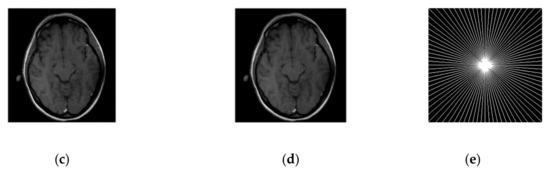

3.2.2. HFEN

The convergence rate has been observed to be efficient. If we compare the SiFo with DLMRI, the SiFo converges at the rate 0.95 whereas DLMRI stops at 1.14 (in the reconstruction of brain image) at the end of the executed number of iteration 15. This shows that the proposed algorithm outperforms DLMRI regarding reasonable noise. So image features for the reconstruction of the brain and phantom images are smooth, clear and free from the effect of aliasing and artifacts as shown in Figure 4.

Figure 4.

Images recovery in a noisy case. (a) Recovered MR image of a brain by SiFo; (b) Recovered MR image of brain by DLMRI; (c) Recovered MR image of phantom by SiFo; (d) Recovered MR image of a phantom by DLMRI; (e) sampling mask in k-space with 10 fold; (f) Reference MR image of a brain.